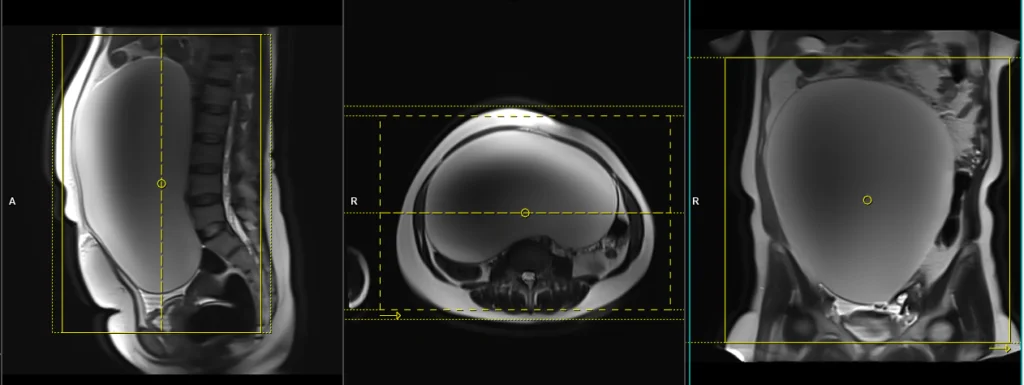

T2 tse coronal large FOV 4mm multiple breath hold / respiratory gated

Plan the coronal T2 TSE slices on the sagittal plane and align the positioning block vertically across the abdomen. Verify the positioning block in the other two planes. In the axial plane, plan the block horizontally across the abdomen, as shown. Ensure that the slices cover the entire pelvic and abdominal mass, extending from the anterior to the posterior. The field of view (FOV) should be sufficiently large to encompass the mass, typically ranging from 350mm to 400mm. Use a right-to-left phase direction with an adequate level of phase oversampling to prevent any wrap-around artifacts.

Due to the large number of slices, the scan is split into three breath-hold acquisitions, each approximately 20 seconds long. Instruct the patient to hold their breath during image acquisition. If T2 TSE scans are unavailable on your scanner, please use TSE-based single-shot sequences (e.g., HASTE). If the patient is unable to hold their breath, consider using respiratory-gated sequences or radial k-space sequences (e.g., BLADE T2).

Parameters